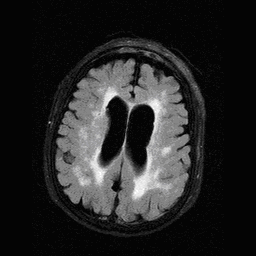

Multiple sclerosis typically appears with lesions presenting in the hemispheric white matter with a periventricular predilection. Other less usual locations for MS lesions include the cerebellum and the pons.

In the later stages the periventricular lesions can become confluent.

The method of choice for the imaging of multiple sclerosis is MRI. MS lesions secondary to their increased water content appear as increased signal intensity lesions on (T2 weighted), PD images and on FLAIR sequence.